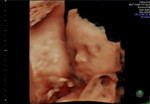

pelekatan menyusui nya bun. kalau disingkat AMuBiDaPi. Aerola masuk yg atas lebih banyak terlihat drpd yg bawah, Mulut membuka, Bibir bawah memble, Dagu nempel di PD, Pipi juga nempel.

belajar pelekatan